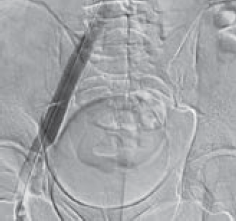

Рис. 9. Контрольная флебография пациента М., 39 лет, от 28.03.2017. Оперативный доступ из левой подколенной вены. Положение пациента на животе. Проходимость обеих подвздошных вен и отсутствие коллатерального кровообращения